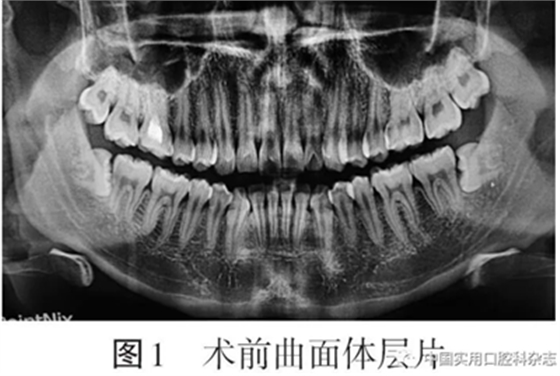

患者男,24岁,以“双侧下颌智齿拔除术后2 d伴胸痛”为主诉于2019-12-25来北京大学口腔医院口腔颌面外科就诊。患者自述2 d前拍摄曲面体层片发现双侧下颌第三磨牙阻生(图1)

否认反复牙龈肿痛病史,于外院拔除双侧下颌第三磨牙,局部麻醉后使用“高速涡轮机分牙拔除”,手术时间约50 min,术中自觉颈部突发疼痛、肌肉抽搐,术后即刻出现胸痛,深呼吸时疼痛加重。术后第1天转动颈部时出现气泡破裂音,偶有头晕,否认发热、恶心、心悸、呼吸困难,于外院静脉输液“美洛西林舒巴坦5 g(每日2次)、奥硝唑200 mL(每日1次)”1 d,自觉症状稍有减轻,于术后第2天来我院就诊要求进一步治疗。临床检查:双侧面颊部自眶下至下颌骨下缘、颈部、锁骨上及胸部轻度肿胀,皮温不高,皮色不红,触诊可及捻发音(图2)